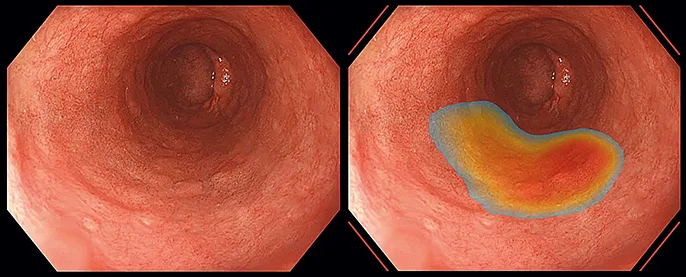

A, Image avec CAD EYE ; B, image avec ENDO-AID.